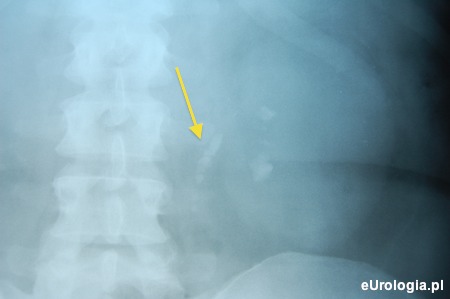

Fot. RTG przeglądowe z widoczną drogą kamiczą tuż poniżej połączenia miedniczkowo - moczowodowego